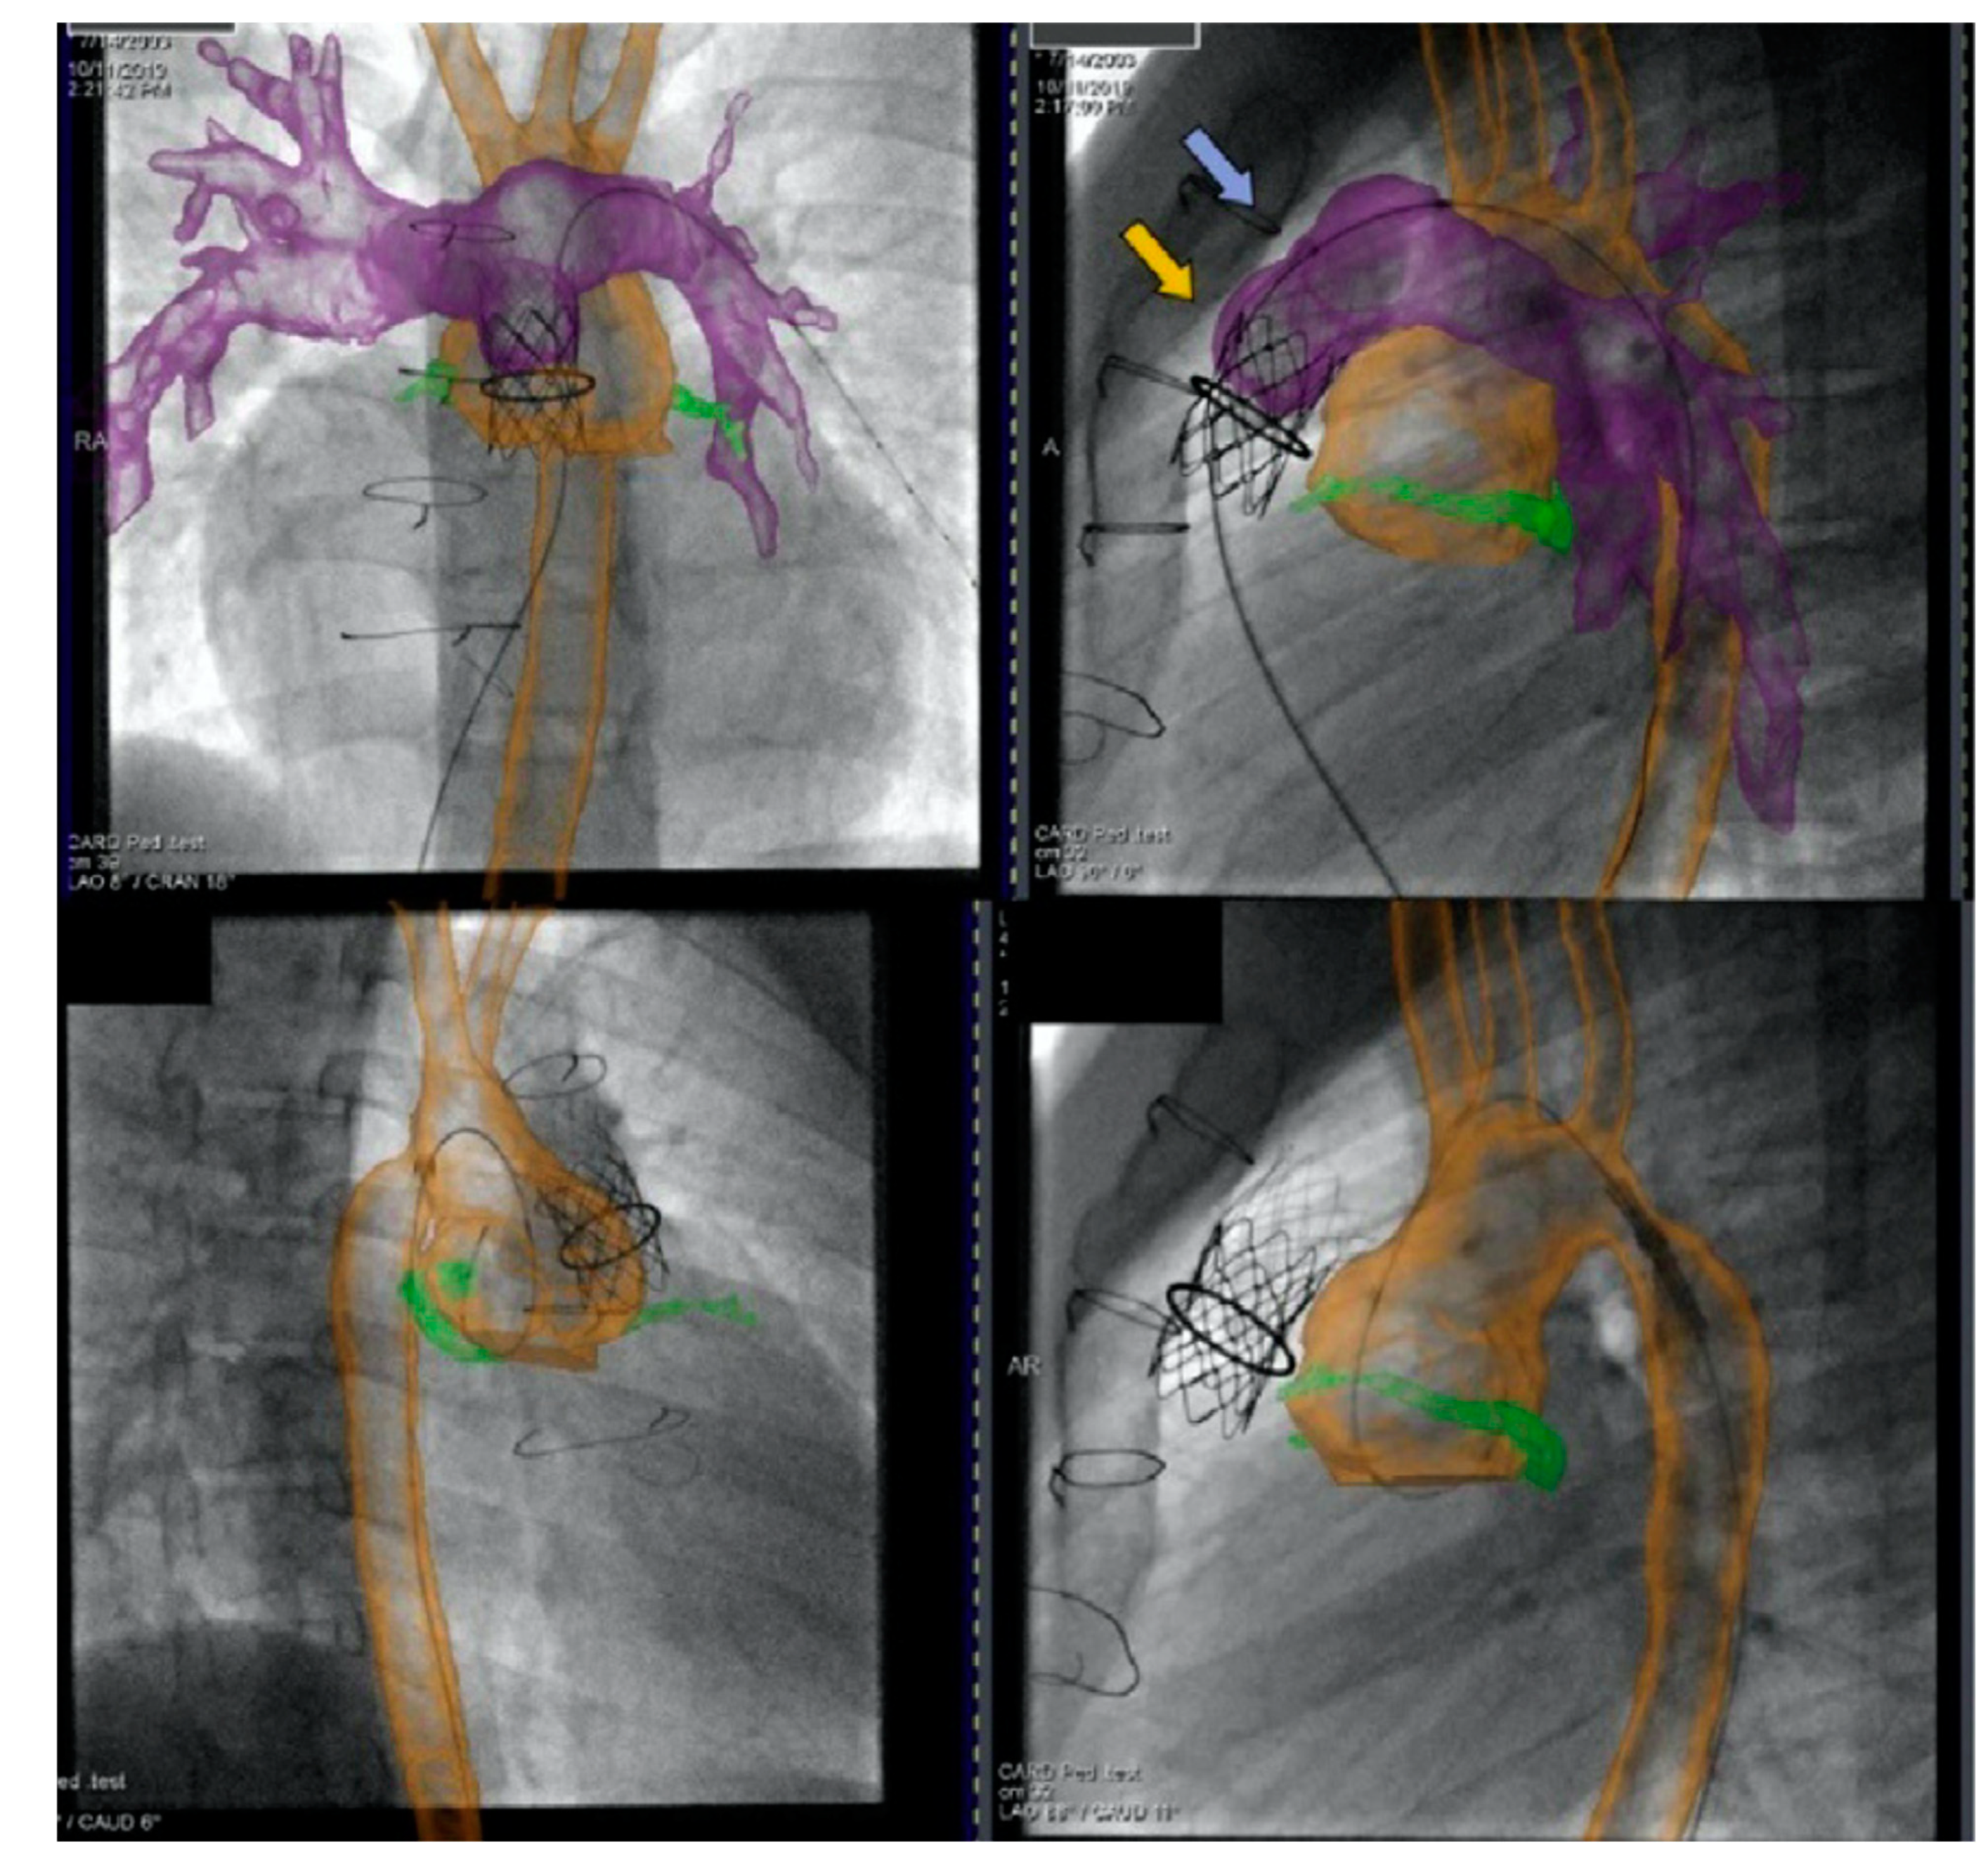

2.4. Cross-Sectional Overlay Fusion in the Catheterization Lab